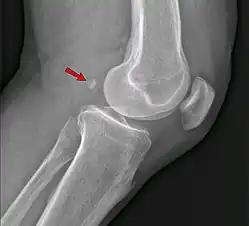

The os ulnostyloideum is an ulnar styloid process that is not fused to the rest of the ulna bone.[6] On X-rays, an os ulnostyloideum is sometimes mistaken for an avulsion fracture of the styloid process. However, the distinction between these is extremely difficult.[6][7] It is alleged that the os ulnostyloideum has a close relationship with or is synonymous with the os triquetrum secundarium.[8]